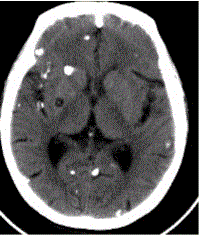

问题 患者男,45岁。头痛、癫痫10余年。查体:无发热,双侧肢体肌力正常。脑电图示双侧额颞叶棘波放电。CT表现如下图。 脑囊虫病按部位分可分为

选项 A.脑实质型 B.蛛网膜下腔型 C.脑室型 D.脑膜型 E.混合型 F.囊泡型 G.钙化型

答案 ACDE